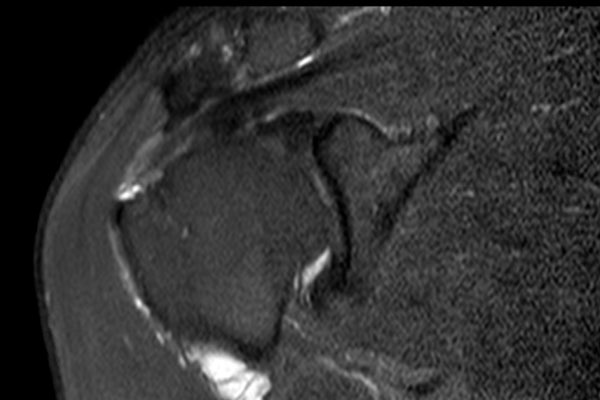

Nhấp vào hình ảnh để phóng to, sau đó cuộn qua các lát cắt.

Có hình ảnh rách toàn bộ chiều dày gân cơ trên gai kèm co rút và teo cơ.

Lưu ý các dải mỡ trong cơ tròn bé, cơ trên gai và cơ dưới gai.